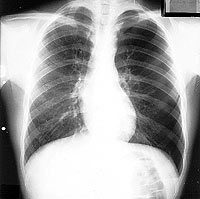

ESQUEMA 46

Al lado izquierdo especialmente al altura delos extremos anteriores de la tercera a quinta costillas, es posible ver el borde del pulmón separado de la pared costal por una zona de densidad aérea en que no hay dibujo pulmonar que es la cámara de un neumotórax. Este es de aproximadamente un 40% del volumen del hemitórax pero aparece menor porque la parte de la cámara que esta por delante y detrás del pulmón no se ve por estar sobrepuesta al pulmón retraído y corazón.